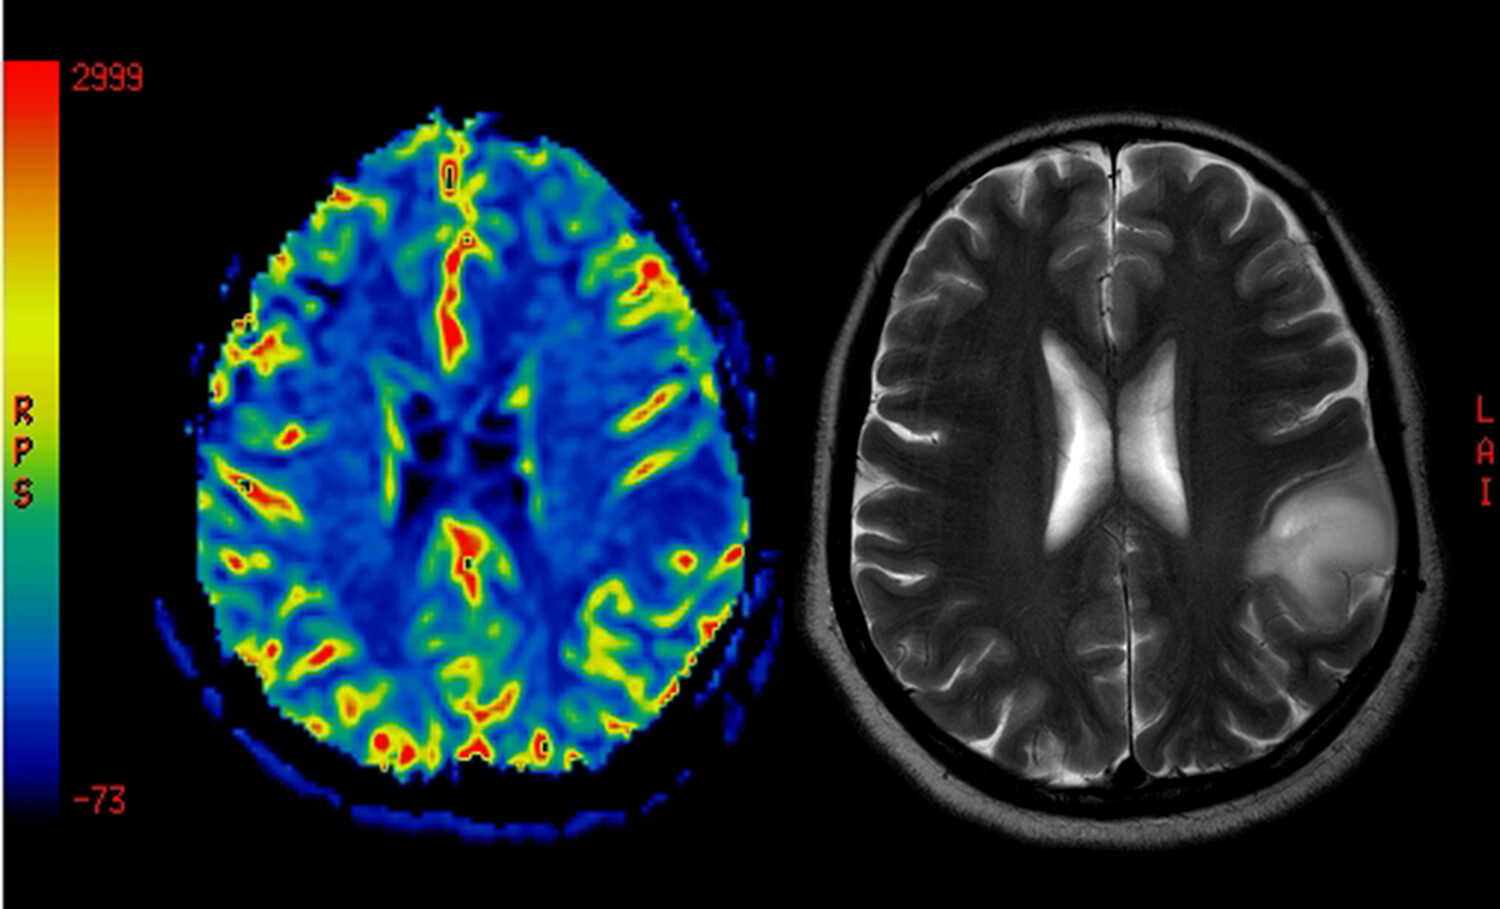

El trabajo no tuvo en cuenta si las diferencias relacionadas con el sexo surgen en etapas tempranas de la vida o si pueden deberse a diferencias hormonales o a las distintas circunstancias sociales a las que hombres y mujeres tienen más probabilidades de enfrentarse. Los «puntos calientes» que más ayudaron al modelo a distinguir los cerebros masculinos de los femeninos incluyen la red de modo por defecto (un sistema cerebral que nos ayuda a procesar información autorreferencial), el cuerpo estriado y la red límbica, que intervienen en el aprendizaje y en cómo respondemos a las recompensas.